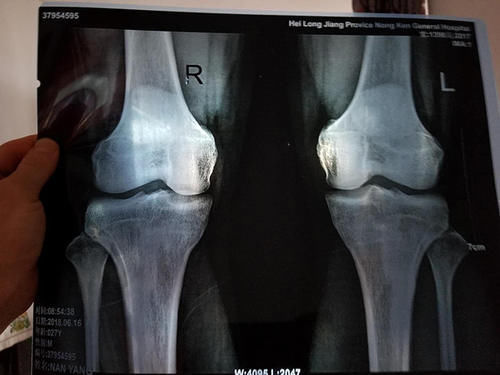

但每个人的身体状况不一样,有的人的骨骼线可能会闭合得比较早一些,所以家长要知道孩子什么时候会停止长高,并抓住这最后的机会进行“全力冲刺”!

正常情况下,骨骼线即将闭合,也就是孩子在停止长身高之前,身体都会发出以下三个信号:

03丨肌肉、骨骼变硬

孩子长身高,主要就是骨骼以及相关肌肉在生长,在他小时候由于需要长高,所以骨骼和肌肉处于比较柔软的状态。

等到他长身高到了尾声,意味着全身的骨骼、肌肉需要定型了,就会变得硬一些。

这个在女生身上可能不是很明显,不过在男孩子身上会特别明显,(当然太胖的男生也不容易发现区别)。